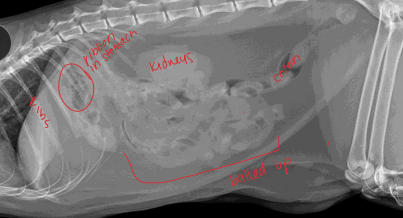

Gastric Dilatation-Volvulus (GDV)

Et: pylorus moves R → ventral → L → dorsal

Dt: lactate trends, ECG (VPC), PT/PTT, RL rads w/ double bubble

Tx: gastric decompress (Trocarization, OG tube), right gastropexy, de-rotation, tube feed, famotidine, pantoprazole, mu opioids, fluids, O2

Considerations for Small Intestinal Surgery

Layers: all stuck together→mucosa, submucosa, muscularis, and serosa

Small Intestinal Foreign Body

Dt: rads (stacking/bunching SI, pneumoperitoneum), US